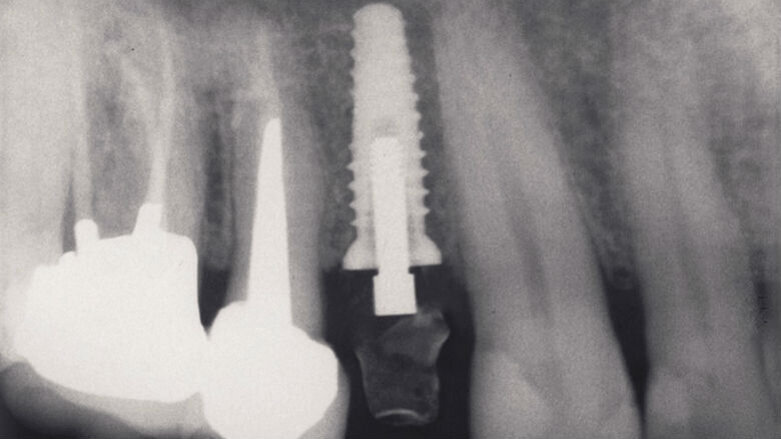

Fig. 2a_Fase protesica provvisoria. Rx endorale di controllo in cui si nota il perfetto posizionamento implantare.